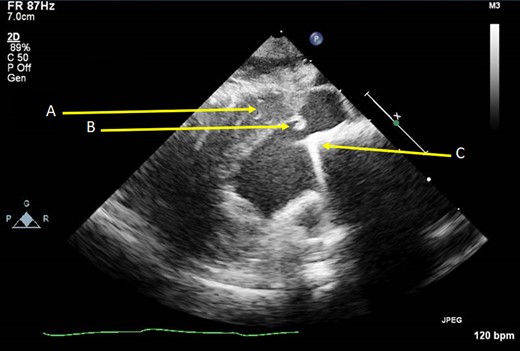

Examining the profile of each valve (Fig. 1), we believe the Carbomedics housing is more predisposed to cause obstruction than the St. Jude. The housing of the Carbomedics prosthesis extends more inferiorly than the St. Jude and potentially into the left ventricular cavity, impinging on the outflow tract. In a patient with coexisting septal hypertrophy, it is clear to see how these two factors alone could cause narrowing. As can be seen in the TTE slice in Fig. 2, the Carbomedics valve is protruding significantly into the LVOT. Severe LVOTO has previously been reported with a Carbomedics mitral valve which was subsequently relieved by replacing the prosthesis with a St. Jude valve [3].

Carbomedics mechanical mitral valve (A) and St. Jude mechanical mitral valve (B) and (C).